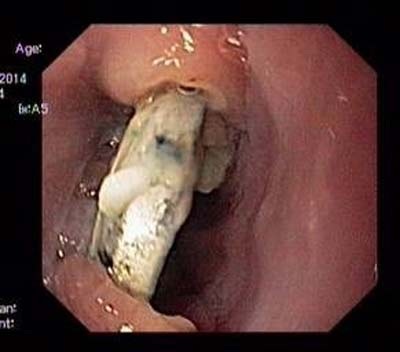

Cục pin nằm trong thực quản đã hoen rỉ. Ảnh do bệnh viện cung cấp.

Ngày 3/10, TS.BS Phan Thị Hiền, Trưởng khoa Nội soi, Bệnh viện Nhi Trung ương cho biết, sau khi nội soi chúng tôi đã gắp thành công một cục pin từ thực quản bệnh nhi T. Cục pin được gắp ra hình tròn, đường kính 1, cm, đã hoen gỉ ở các cạnh. Thực quản bệnh nhi bị loét sâu, có giả mạc và rớm máu.